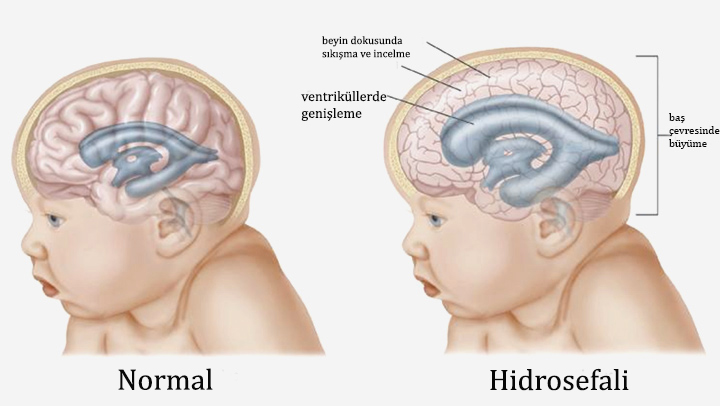

Beyin tümörü uyku hali. Yetişkinlerde ikincil beyin tümörleri birincil beyin tümörlerinden çok daha yaygındır. Ancak şikayetler çok daha çeşitlilik gösterebilir. 1925 yılından beri bilinen bu beyincik tümörü çok ayrı hücresel ve klinik özellikeri olan ve oldukça habis karekterli bir beyincik tümör tipidir beyinciğin çocuklarda en sık tümörü olup tüm primer beyin tümörlerininin 4 10 teşkil ederler. Patoloji alındı ondada tam teşhis konulmadı.

Uykuyu kontrol eden sinirler beyin sisteminde yer aldığı için sürekli uyku problemini çözmek için nöroloji bölümüne gitmeniz gereklidir. İkincil beyin tümörleri en sık kanser öyküsü olan kişilerde görülür. Denge kaybı uyku hali gözde görme sorunları duyma sorunları el ya da ayaklarda his sorunları ruhsal değişiklikler halüsinasyonlar görebilir yemek yeme sorunları yutkunma sorunları yemek yeme sorunları halsizlik trombosit düşüklüğü lökosit. Sadece uyku hali be yorgunluğu vardı.

Sonrasında bulantı kusma şuur dalgalanmaları uyku hali baş dönmesi ve nöbet geçirme vücudun farklı bölgelerinde kuvvetsizlikler iştahsızlık unutkanlık gelmektedir. Bunların en başında yeterince uyumamaktır. Ancak çocukluk yaşı tümörlerin 15 20 sini teşkil etmektedir. Beyin tümörü uyku yapar mı.